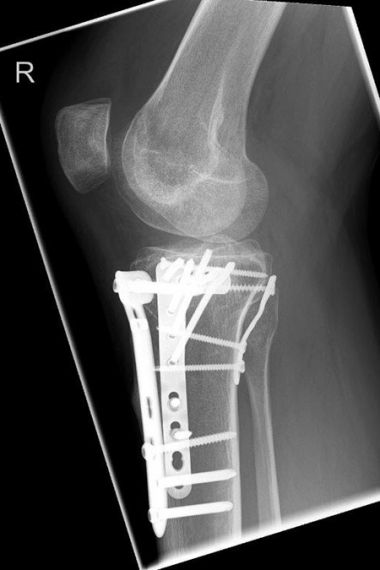

Bild Patientin 3 Monate nach Tibiakopffraktur

„Ich bin an einem Sonntag mit meinem Fahrrad gestürzt und dachte zuerst gar nicht, dass das so schlimm gewesen ist. Der Schienenbeinkopf war jedoch auf der Außenseite gebrochen und die Gelenkfläche richtig eingedrückt. Das konnte man auf den CT- Bildern gut sehen. Nach der Operation habe ich dann eine ganze Zeit entlastet aber schon bewegt. Jetzt 3 Monate nach der Verletzung geht es eigentlich schon ganz gut.“

Im April 2022 versorgter außenseitiger Schienenbeinkopfbruch (Tibiakopffraktur) bei einer 35-jährigen Patientin. Bei der Versorgung wurde anhand der CT – Untersuchung die außenseitige kniekehlenwärts gelegene Gelenkflächenabsenkung wieder angehoben und mit Knochen unterfüttert. Intraoperativ wurde mit Hilfe der Arthroskopie die Gelenkfläche überprüft. Anschließend wurde die Rekonstruktion durch die seitliche und hintere Platte sowie zusätzliche Schrauben stabilisiert. Nach der Operation konnte das Knie steigernd bewegt und zunächst mit einer Teilbelastung an Unterarmgehstützen belastet werden. Nach 3 Monaten ist die freie Belastung bei guter Beweglichkeit wieder erzielt worden.